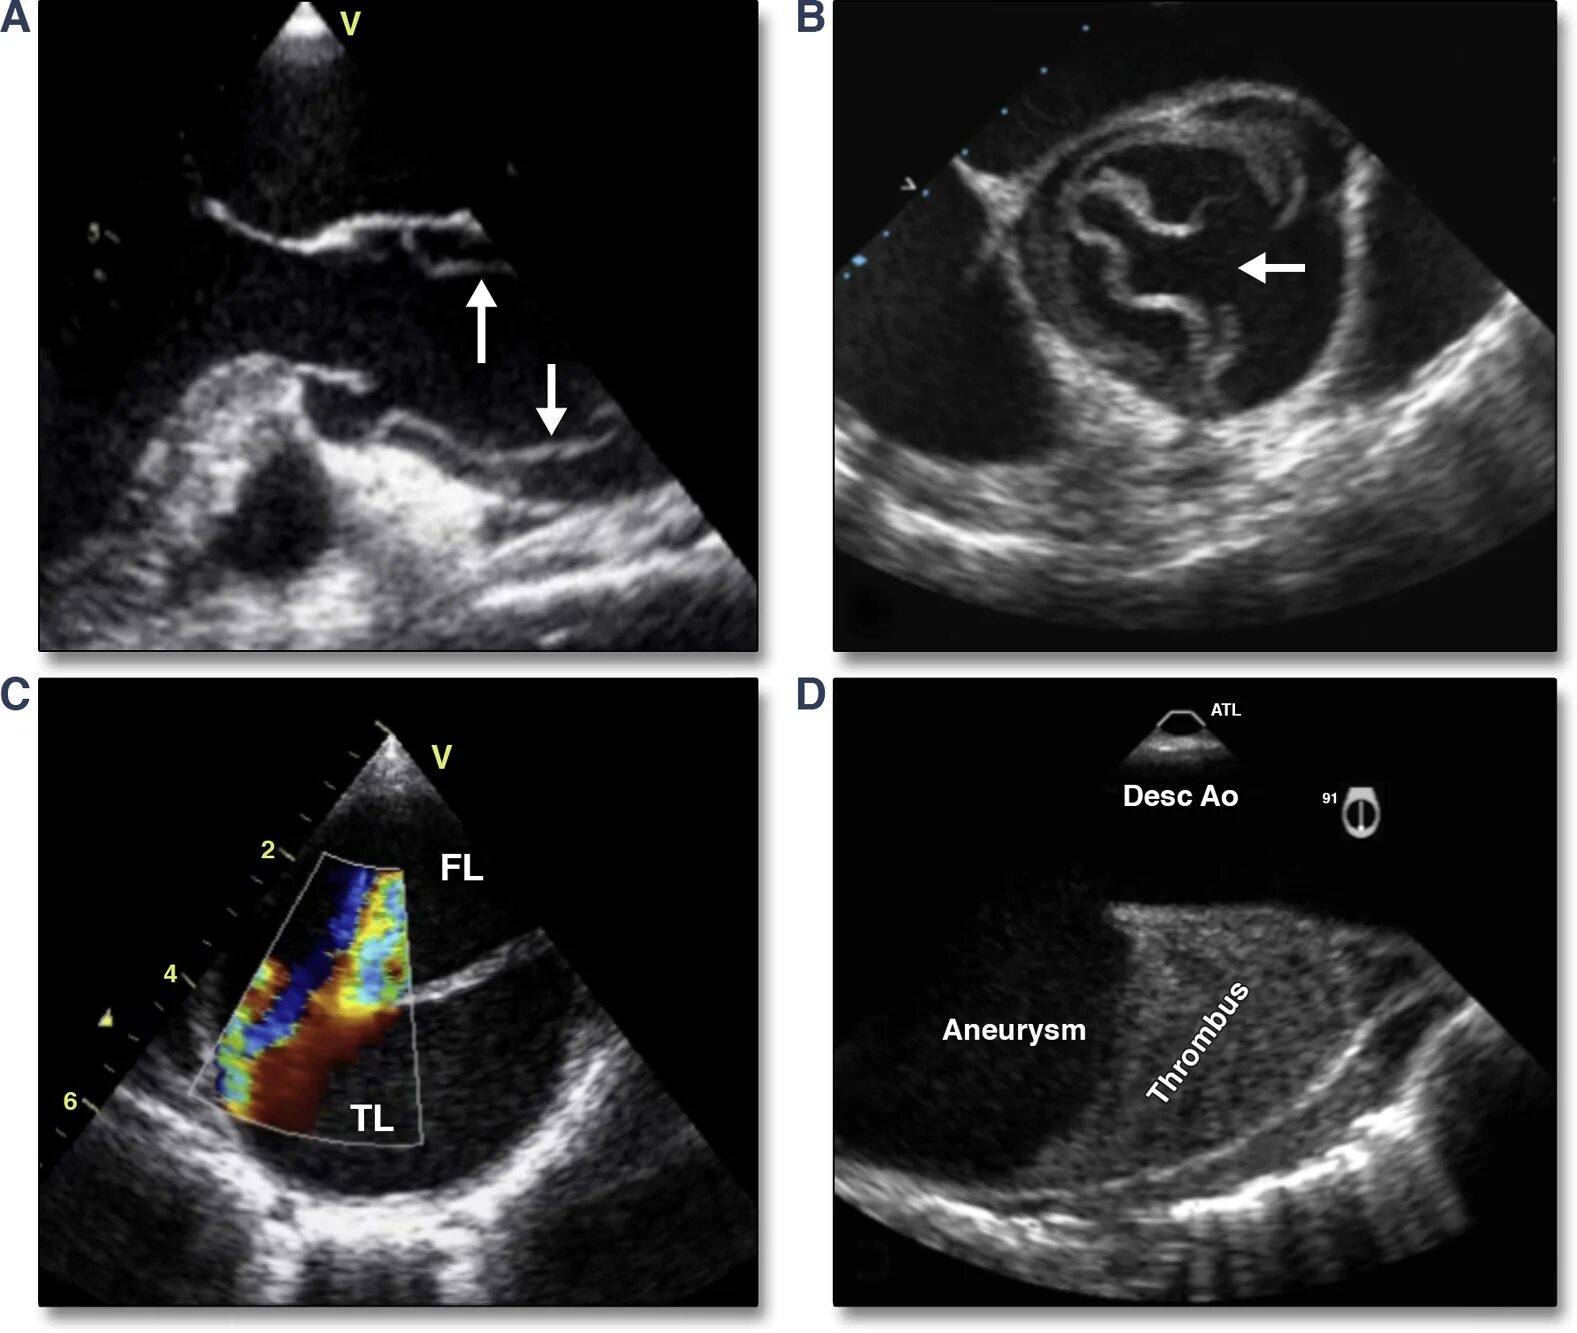

Уплотнение аортальных створок